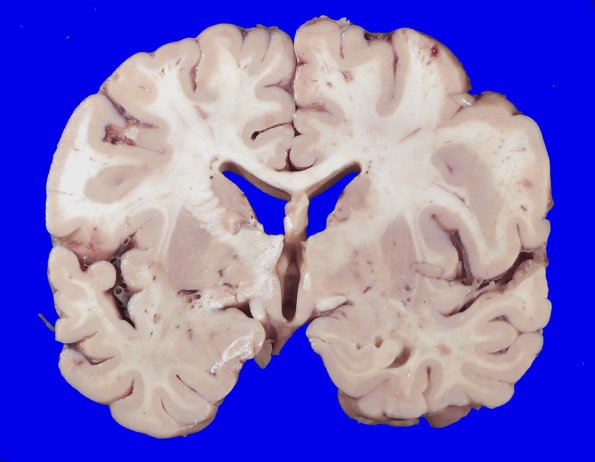

23F1-5 There are numerous lesions demonstrated in coronal sections of the cerebral hemispheres.